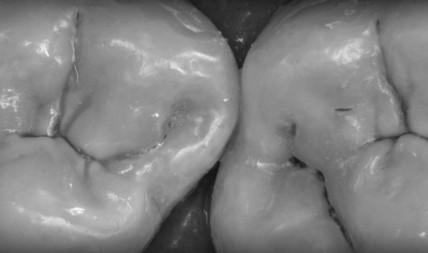

Виктор Щербаков признанный на международном уровне специалист по высокохудожественной прямой реставрации.

Всемирно известный лектор и автор множества уникальных обучающих программ для стоматологов. Дизайнер, автор легендарных высокохудожественных дентальных фотографий Основатель бренда стоматологических аксессуаров ZenGears и международного образовательного проекта ZenCourses.